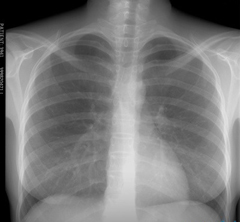

Флюорография легких – исследование органов грудной клетки с помощью рентгеновских лучей, проникающих через легочную ткань и переносящих на пленку посредством флюоресцирующих микроскопических частиц рисунок легких.

Органы грудной клетки по-разному поглощают излучение, поэтому снимок выглядит неоднородным. Сердце, бронхи и бронхиолы выглядят светлыми пятнами, если легкие здоровые, флюорография отобразит легочную ткань однородной и равномерной. А вот если в легких воспаление, на флюорографии, в зависимости от характера изменений воспаленной ткани, будут видны либо затемнения – плотность легочной ткани повышена, либо будут замечены высветленные участки – воздушность ткани достаточно высока.

Результаты флюорографии готовят обычно несколько дней, после этого полученную флюорограмму рассматривает рентгенолог и в том случае если была проведена флюорография здоровых легких, на дальнейшее обследование пациента не отправляют. В противном случае, если рентгенолог обнаружил изменения легочной ткани, человека могут отправить для уточнения диагноза на рентгенографию или в противотуберкулезный диспансер.

К снимку, полученному после флюорографии легких, прилагается заключение рентгенолога, в котором могут значиться такие формулировки:

Корни расширены, уплотнены. Корни легких формируют лимфатические узлы и сосуды, легочная вена и артерия, главный бронх, бронхиальные артерии. Уплотнение в этой области при общем удовлетворительном состоянии здоровья указывает на бронхит, воспаление легких и другие воспалительные, возможно хронические процессы.

Корни тяжисты. Чаще всего такое заключение после проведенной флюорографии легких указывает на бронхит или другой острый/хронический процесс. Такое изменение легочной ткани часто обнаруживают на флюорографии легких курильщика.

Усиление сосудистого (легочного) рисунка. Легочный рисунок образуют тени вен и артерий легких и если кровоснабжение из-за воспаления усилено, а это может и бронхит, и начальная стадия рака, и воспаление легких, на флюорографии заметно, что сосудистый рисунок слишком выделяется. Кроме этого, выявленное на флюорографии легких усиление рисунка может указывать и на проблемы сердечнососудистой системы.

Фиброзная ткань. Обнаруженная соединительная ткань в легких говорит о том, что ранее человек перенес заболевание легких. Это могла быть травма, инфекция или операция. Несмотря на то, что подобное заключение указывает на потерю части легочной ткани, такой результат часто дает флюорография здоровых легких.

Очаговые тени. Так называют затемнения области легких на флюорограмме размером до 1 см. Если очаги обнаружены в нижних и средних отделах легких, это может быть пневмония. На сильное воспаление указывает такая формулировка в заключении флюорографии легких: «неровные края», « слияние теней», «усиление сосудистого рисунка». Если же очаги больше ровные и плотные, значит, воспалительный процесс идет на спад. Если очаги обнаружены в верхних отделах легких, это может указывать на туберкулез.

Кальцинаты. Так называют округлые по форме тени, напоминающие по плотности костную ткань. Опасности подобные явления не представляют, а лишь говорят о том, что у пациента был контакт с больным пневмонией, туберкулезом, зараженным паразитами и т.д., но организм не дал развиться инфекции, а изолировал бактерии-возбудители под отложениями солей кальция.

Плевроапикальные наслоения, спайки. Обнаруженные на флюорографии легких структуры из соединительной ткани – спайки, в большинстве случаев также не требуют лечения, а лишь указывают на воспаление в плевре в прошлом. Иногда спайки вызывают болезненные ощущения, в этом случае следует обратиться за медицинской помощью. Плевроапикальными наслоениями называют утолщения верхушек легких, и они также указывают на то, что человек перенес воспаление, затронувшее плевру (чаще всего это туберкулез).

Синус запаян или свободен. Плевральные синусы – это образованные плевральными складками полости. Если легкие здоровые, флюорография покажет, что синусы свободны. Но иногда наблюдаются скопление жидкости (в этом случае требуется лечение) или запаянные спайки.

Изменения диафрагмы. Такое заключение после флюорографии легких дают в том случае, если у человека обнаружена аномалия диафрагмы, которая могла развиться из-за плохой наследственности, ожирения, деформации спайками, после перенесенных плеврита, болезней печени, пищевода, кишечника или желудка. В этом случае обычно назначают дополнительное обследование.

Тень средостения смещена или расширена. Средостением называют пространство между легкими и органы в нем находящиеся - это аорта, пищевод, сердце, трахея, лимфатические сосуды, узлы, железа вилочковая. Расширение тени средостения наблюдается из-за увеличения сердца, гипертонии, сердечной недостаточности, миокардита. Смещение средостения может указывать на неравномерное скопление воздуха или жидкости в плевре, большие новообразования в легких. Подобное заключение флюорографии легких указывает на то, что необходимо немедленно пройти дообследование и лечение.